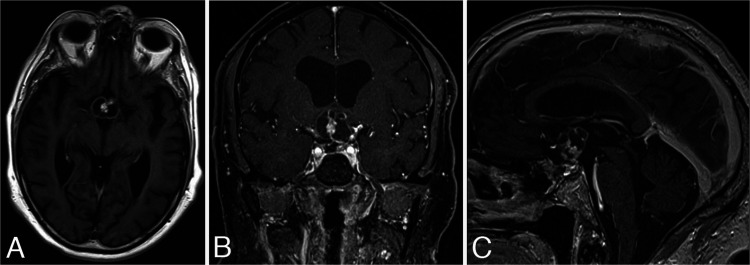

Seven years after surgery, or 3 years after the last follow-up, the patient came back complaining of blurred vision. He had decreased visual acuity in the right eye and a bitemporal hemianopsia. Also, the MRI showed a 2.3 × 2 × 1.9–cm heterogeneous cystic mass at the sellar region, compressing the optic chiasm and involving the cavernous sinus (Fig. 4). Ventricles were also enlarged compared to the previous scan. The presumed diagnosis was a recurrent and largely cystic NPA. Given the patient’s age and frail appearance, as well as the ongoing coronavirus disease 2019 (COVID-19) pandemic, we sought to address his main symptom of visual loss by placing a catheter into the cyst, draining the cyst, and attaching the catheter to an Ommaya reservoir. This was unsuccessful in that the catheter appeared to curve around the cyst capsule (Fig. 5). After surgery, the patient’s mental status declined despite adequate hormonal replacement. To address his visual loss, endoscopic transsphenoidal resection of the tumor was performed with opening of the cyst, visualization of the third ventricle, and removal of the solid tumor. This tumor proved to be a PCP with a BRAF V600E mutation (Fig. 3B).

FIG. 4.

MRI seven years after surgery. Axial (A), coronal (B), and sagittal (C) contrast-enhanced T1-weighted images. A 2.3 × 2 × 1.9–cm complex mass with cystic and solid components is noted at the sellar region, compressing the optic chiasm and involving the cavernous sinus. In retrospect, the imaging features of this cystic lesion are consistent with a CP.